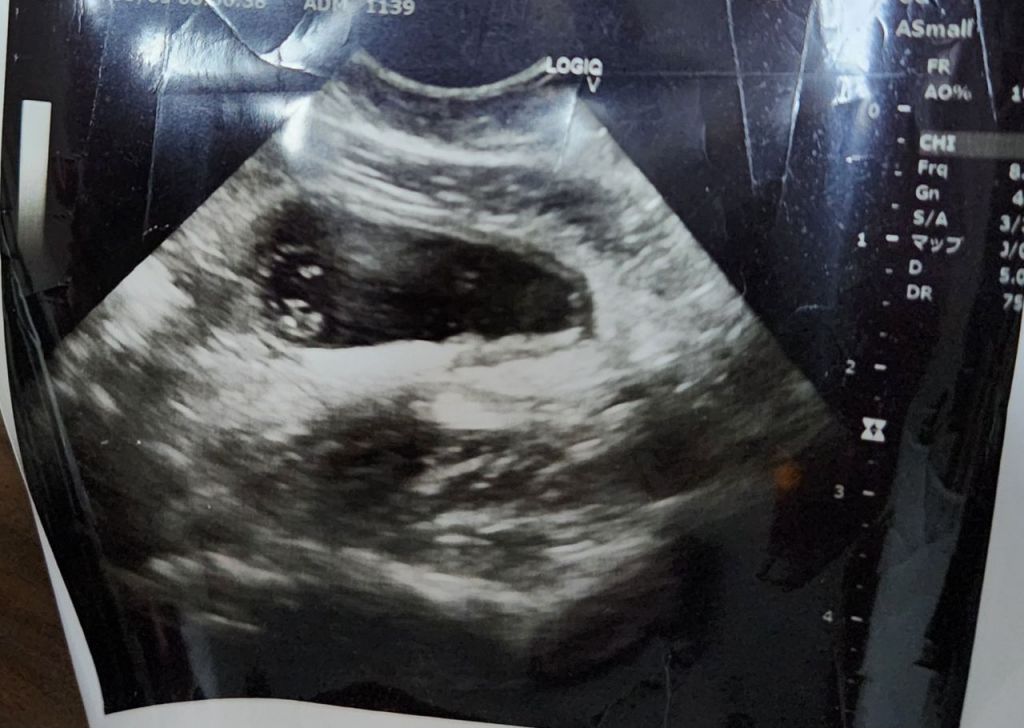

일본 중고거래 플랫폼 메르카리에서 판매됐던 태아 사진. 엑스(X·옛 트위터) 캡처

일본 중고거래 플랫폼 메르카리에서 판매 중인 태아 초음파 사진.

한편 이 같은 조치에도 플랫폼에는 태아 초음파 사진 게시물이 여전히 게재돼 있다. 이날 메르카리에서 '태아 초음파 사진'으로 검색하면 '날짜와 이름 가공 가능, 임신 7주'라는 상품이 약 6000엔(5만6000원)에 거래되거나, '임신 5개월 초음파 사진'이 3000엔(2만8000원)에 올라온 사례가 확인됐다.